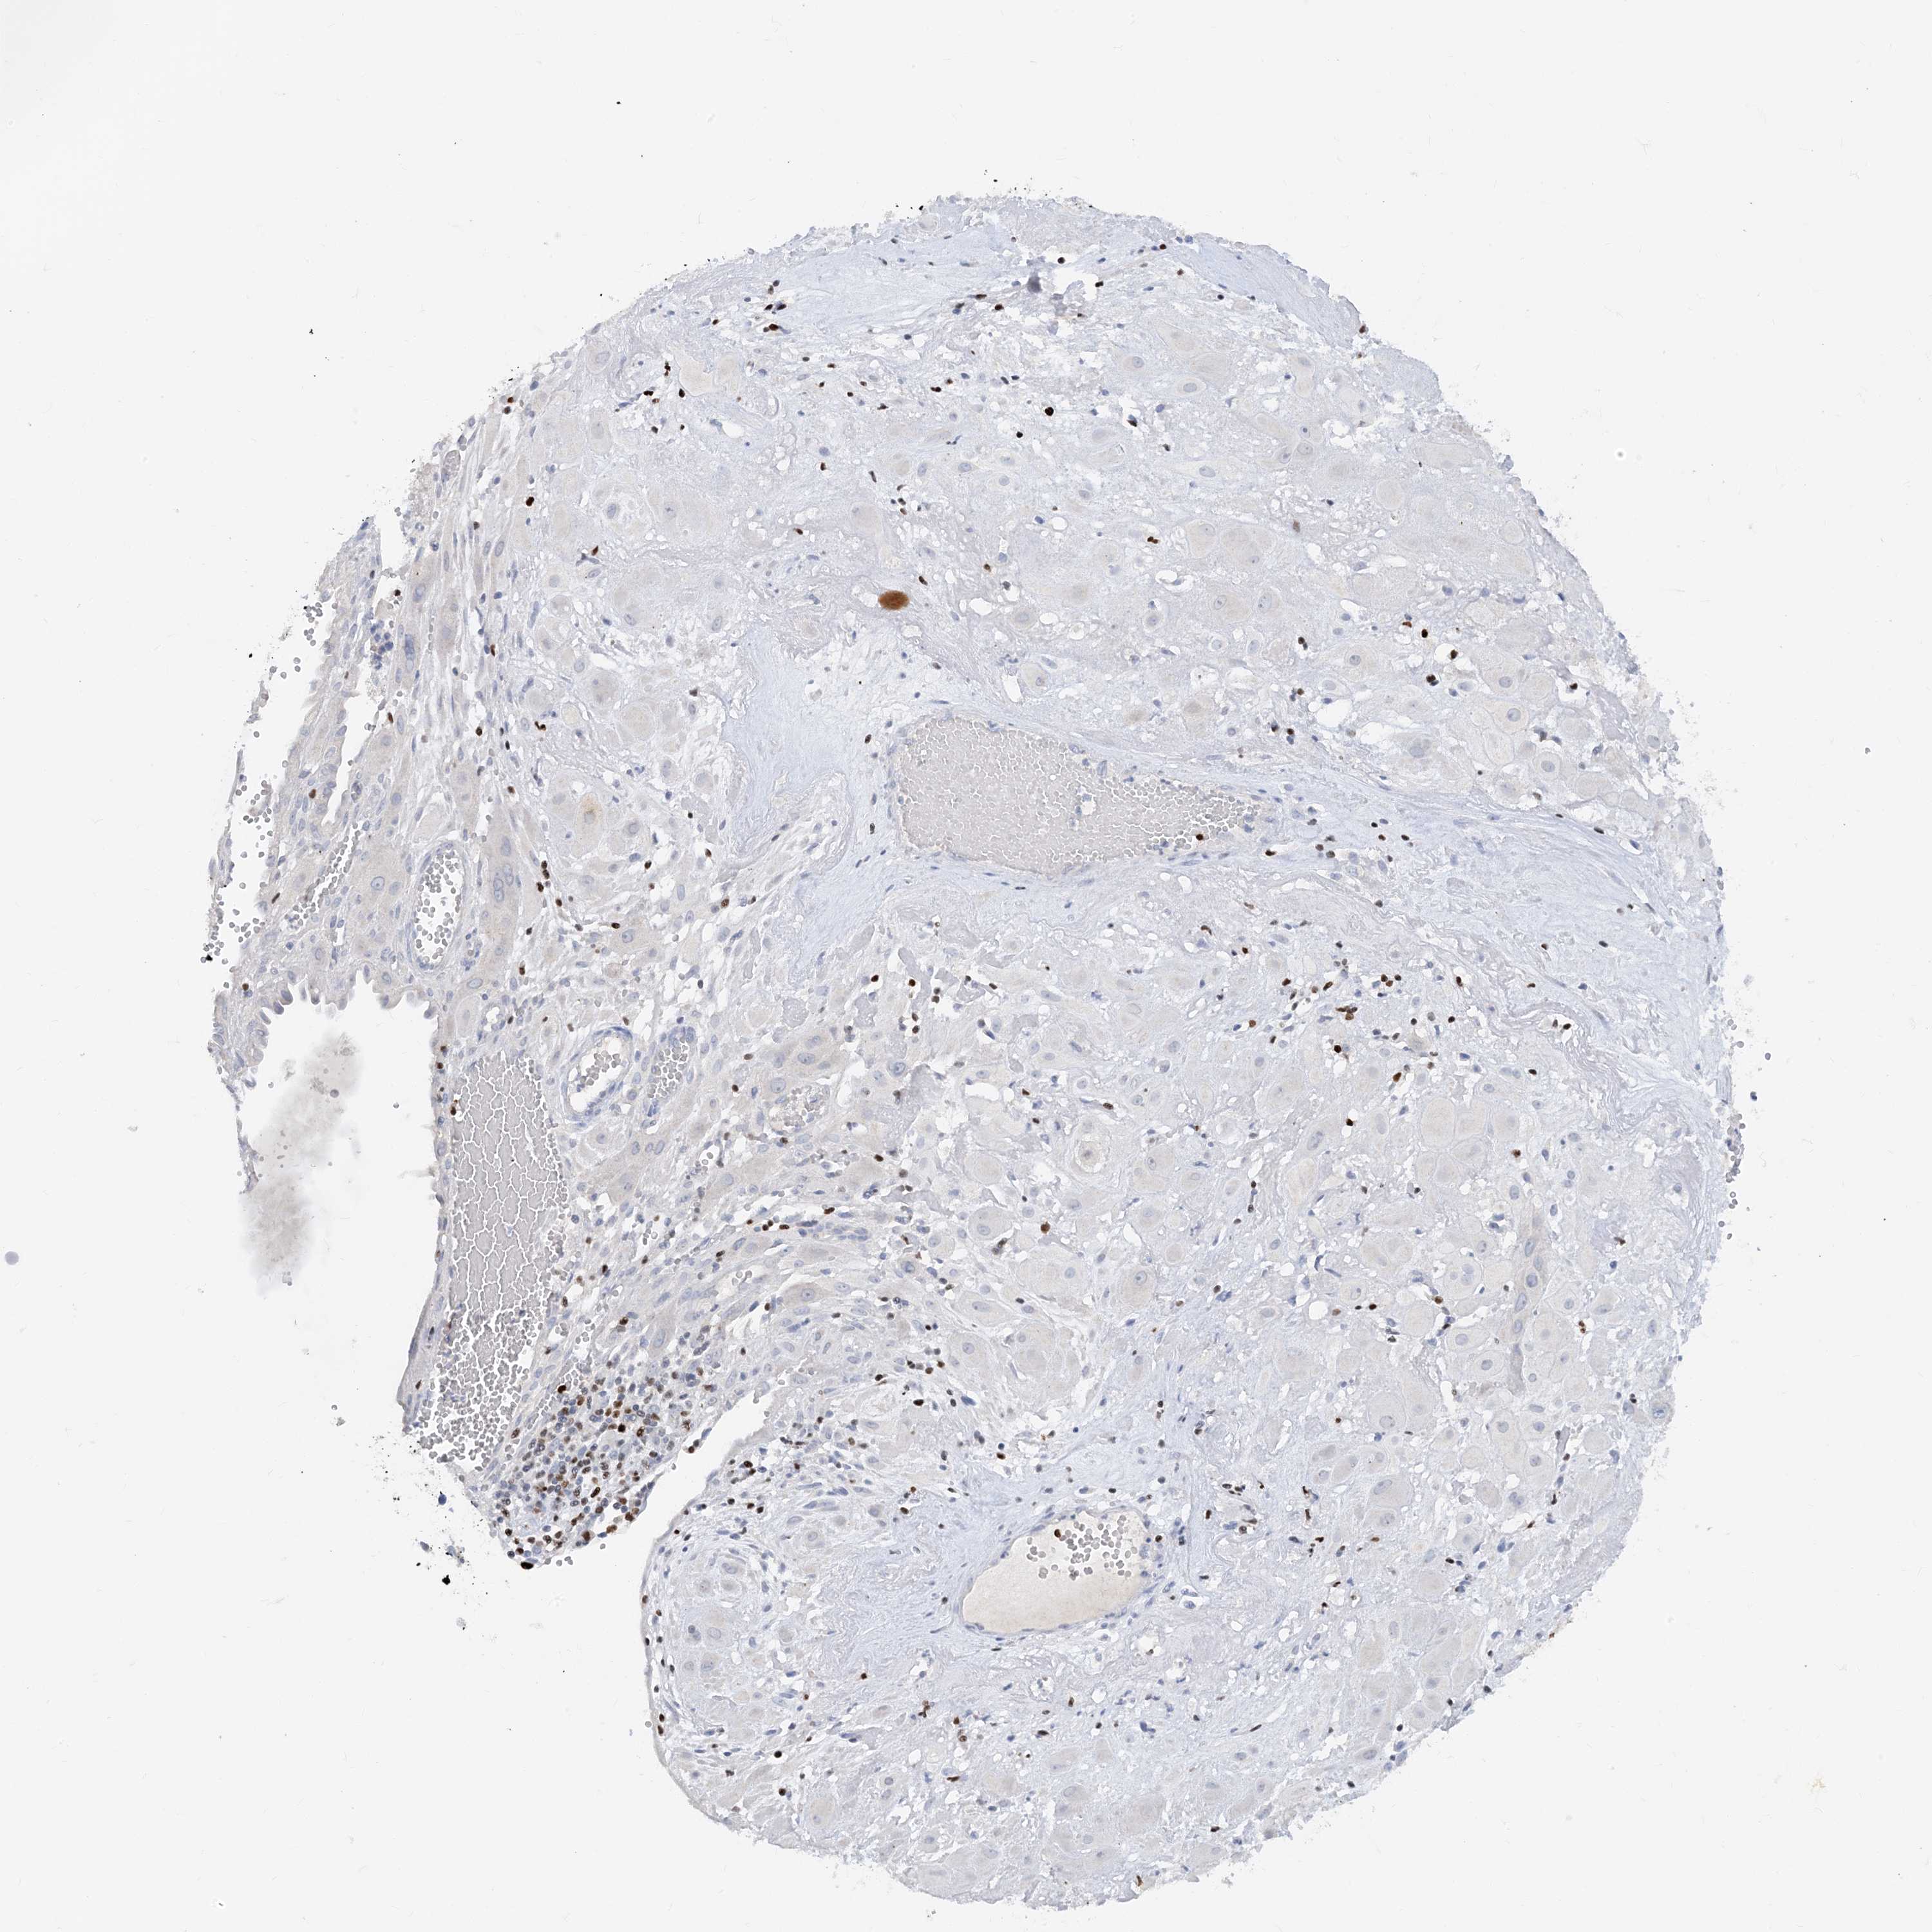

TBX21